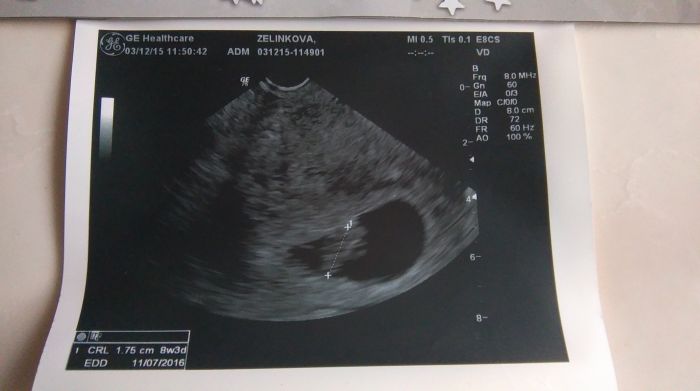

Tady je fotka

sestra říkala že ma starej ultrazvuk že muj doktor má dobrej ultrazvuk ona že má starý ale měřit by měl dobre taky nechápu tu otřesnou fotku u Lucky jsme měla od toho samého doktora který je nemocný krásnou fotku v 8 tt a ted toto? dyt co to je nějakej špinavej flek?

je to tedy flek... ale já bych řekla, že je to dost možná i špatně změřeno. okraje jsou dost rozmazané a aktuálně je to jinak u každé setiny milimetru. Ještě si zajeď a pak dej vědět.